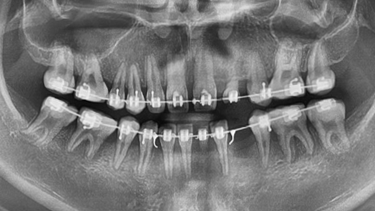

20세 남환으로 2013년 다수 영구치의 선천적 결손으로 내원하 여, 성장을 관찰하면서 교정치료를 진행하였다 [그림 10].

교정치료가 거의 완료될 시점에서 영구치 결손 부위인 #22, 23, 33, 34부위에 4개의 임플란트를 식립하기로 계획하였다 [그림 11].